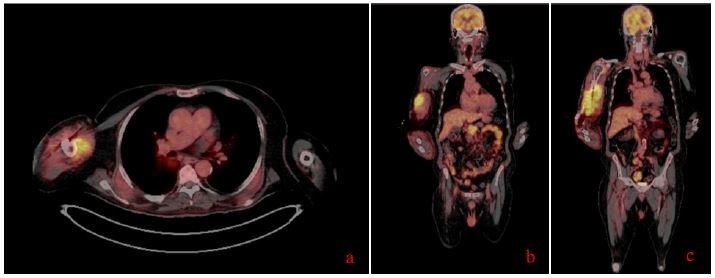

To comprehensively assess the patient’s condition, a PET-CT scan was performed (september 2024). This imaging modality revealed an additional suspicious mass in the pancreas, which had not been identified on prior imaging studies.

Figure 1: (A-C) Different sections of the patient’s PET CT scan showing an extensive, intensely hypermetabolic tissue lesion in the pancreatic head, along with a large, intensely hypermetabolic skeletal muscle lesion on the right side, with associated humeral involvement.